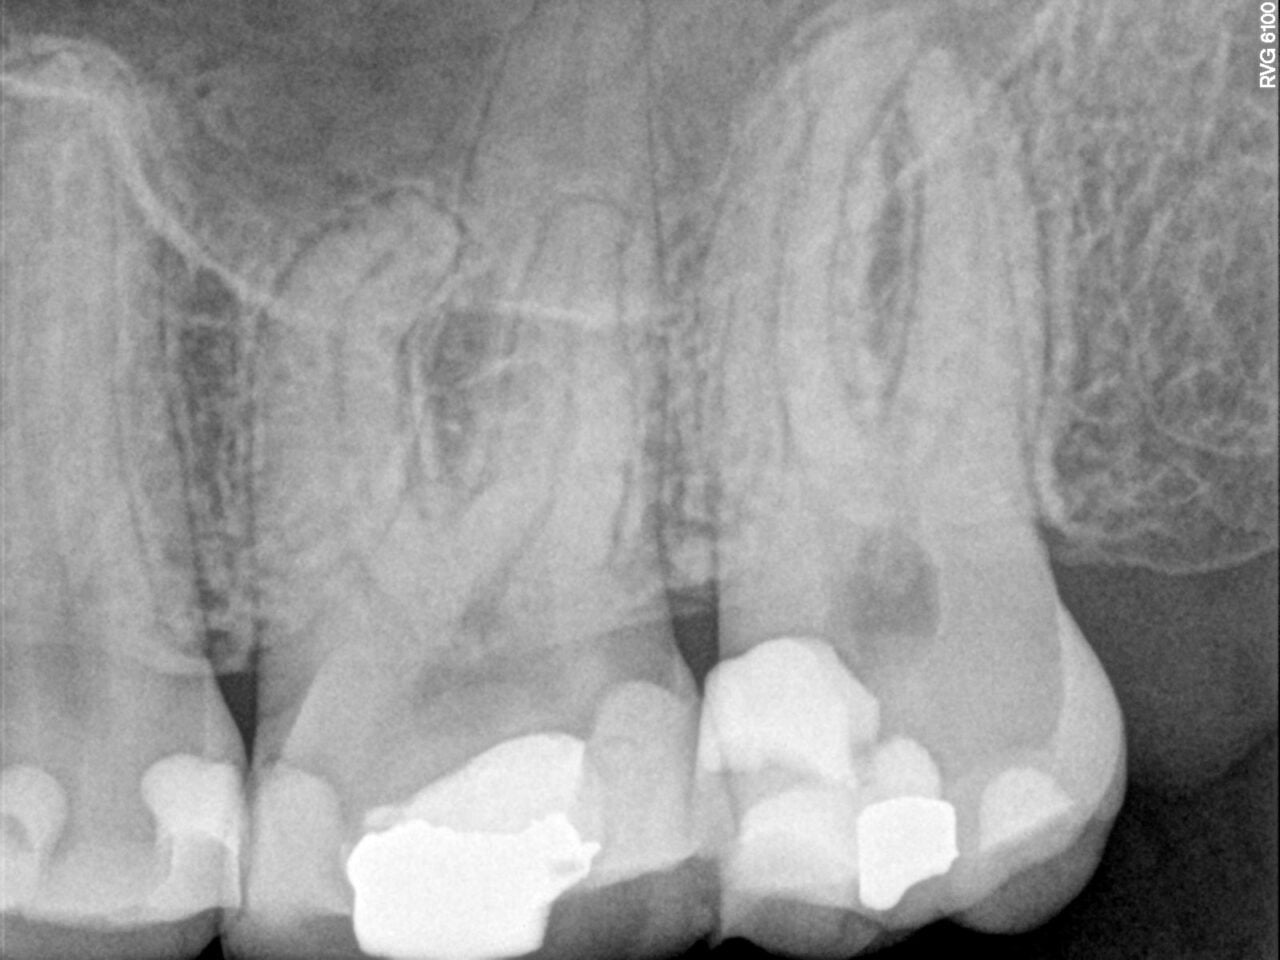

Patient A: Step-by-step in pictures

Once the glide paths had been prepared using the FQ Glider, Dr. Michiels shaped the canals with the FQ 025 file (.04 taper) to working length, followed by the FQ 035 file (.04 taper) to finalize shaping. The selected taper depended on the obturation method planned for the case.

For single-cone obturation, the .04 taper is preferred, as it conserves more of the natural tooth structure. For warm obturation techniques, however, a .06 taper is usually the more suitable option.

Throughout the treatment, irrigation played a vital role. Sodium hypochlorite (5.25%) was used during shaping, followed by a final rinse with 40% citric acid before obturation. The treatment was completed using the single-cone technique with Komet BioSeal, ensuring an efficient and reliable result.